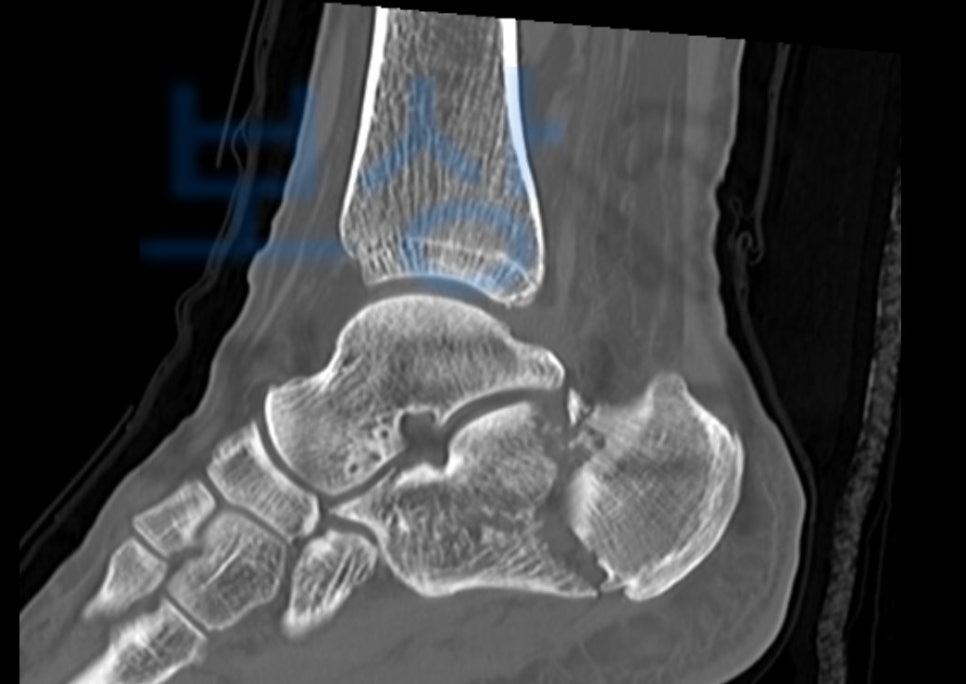

위 사고로 정밀검사를 진행하게 되었고 그 결과

진단서를 보시면

양 발의 종골(calcaneus) 골절